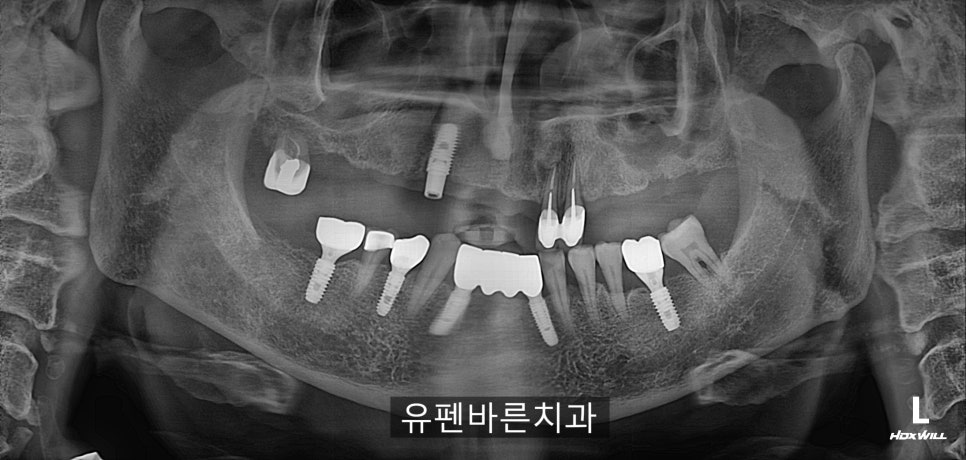

Initial Panorama

환자분께서는

기존 틀니의 고정력이 떨어져

식사 하기가 불편하셔서

아래 임플란트 하신것처럼

윗니를 전체 임플란트로 대체하고 싶어 하셨어요.

틀니를 오랜기간 사용 하셨고

뼈 높이가 일정하지 않은데다가

혈액관련 복용중인 약이 있으시면서

고령이셔서

쉽지 않은 시작이었습니다 ㅠ.ㅠ

그러나

원장님께서는

3차원적으로

뼈두께, 위치, 각도등을

확인할수 있는

CT 를 찍어보더시니

전체 잠실새내임플란트 치료가

가능하다고 하셨어요!